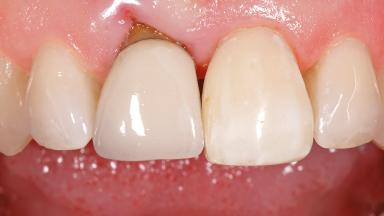

Early Placement of an Implant in a Maxillary Right Central Incisor Site

This 41-year-old female patient was referred to the clinic for the replacement of the right central incisor, since the tooth had developed a root fracture in the long axis that made extraction necessary. The healthy, non-smoking patient was first seen with the tooth still in place. A detailed Esthetic Risk Assessment was performed.The patient was worried about her dental esthetics and had high expectations for a successful treatment outcome from an esthetic point of view. The patient had a medium lip line that displayed parts of the gingiva in the anterior maxilla upon smile.

Defining Characteristics One missing tooth to be replaced by an implant-borne crown

Esthetic Risk High